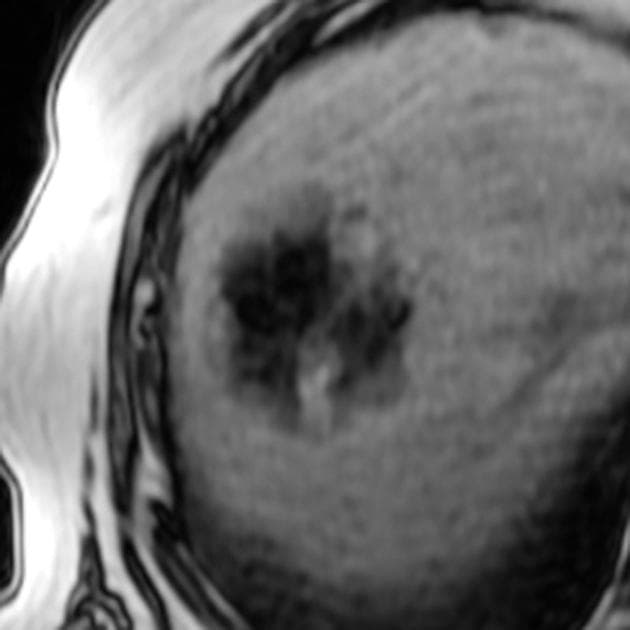

Axial T1 C+

MRI•Axial T1 C+•1 / 29

- Tổn thương lớn nhất nằm ở thuỳ trái gan, phân đoạn 3, có tín hiệu đồng tín hiệu (isointense) so với nhu mô gan trên hình ảnh cộng hưởng từ (MRI) trọng T1 và không giảm tín hiệu trên hình ảnh out-of-phase, điều này không gợi ý có sự hiện diện của mỡ.

- Trên hình ảnh trọng T2, tổn thương có tín hiệu đồng tín hiệu đến hơi tăng tín hiệu so với gan, với vùng trung tâm tăng tín hiệu, phù hợp với sẹo trung tâm.

- Tổn thương cho thấy tăng quang động mạch, trong đó vùng sẹo trung tâm không tăng quang, nhưng đến thì muộn thì sẹo trung tâm xuất hiện tăng quang chậm.

- "Tăng sản khu trú dạng nốt (FNH) thường tăng quang động mạch, có sẹo trung tâm và sẹo này tăng quang chậm ở thì muộn trên MRI."

Tăng sản khu trú dạng nốt (FNH) là tổn thương gan lành tính, thường gặp ở phụ nữ trẻ đến trung niên, thường được phát hiện tình cờ khi chụp hình. Tổn thương đặc trưng bởi sẹo trung tâm với các vách xơ tỏa ra và cấu trúc mạch máu bất thường. Trên MRI, FNH có tín hiệu đồng tín hiệu ở T1, hơi tăng tín hiệu ở T2, tăng quang mạnh ở thì động mạch và tăng quang chậm ở sẹo trung tâm ở thì muộn. Nhiều ổ FNH có thể xuất hiện đơn độc hoặc trong hội chứng FNH nhiều ổ hoặc bệnh di truyền giãn mạch máu dạng telangiectasia xuất huyết (HHT), bệnh này liên quan đến các dị dạng mạch máu ở cơ quan khác. Việc phân biệt với u tuyến tế bào gan rất quan trọng vì u tuyến có nguy cơ xuất huyết và ác tính hóa. Việc không có mỡ, có sẹo trung tâm và kiểu tăng quang đặc trưng giúp nghi ngờ FNH. Sinh thiết hiếm khi cần thiết nếu hình ảnh điển hình.